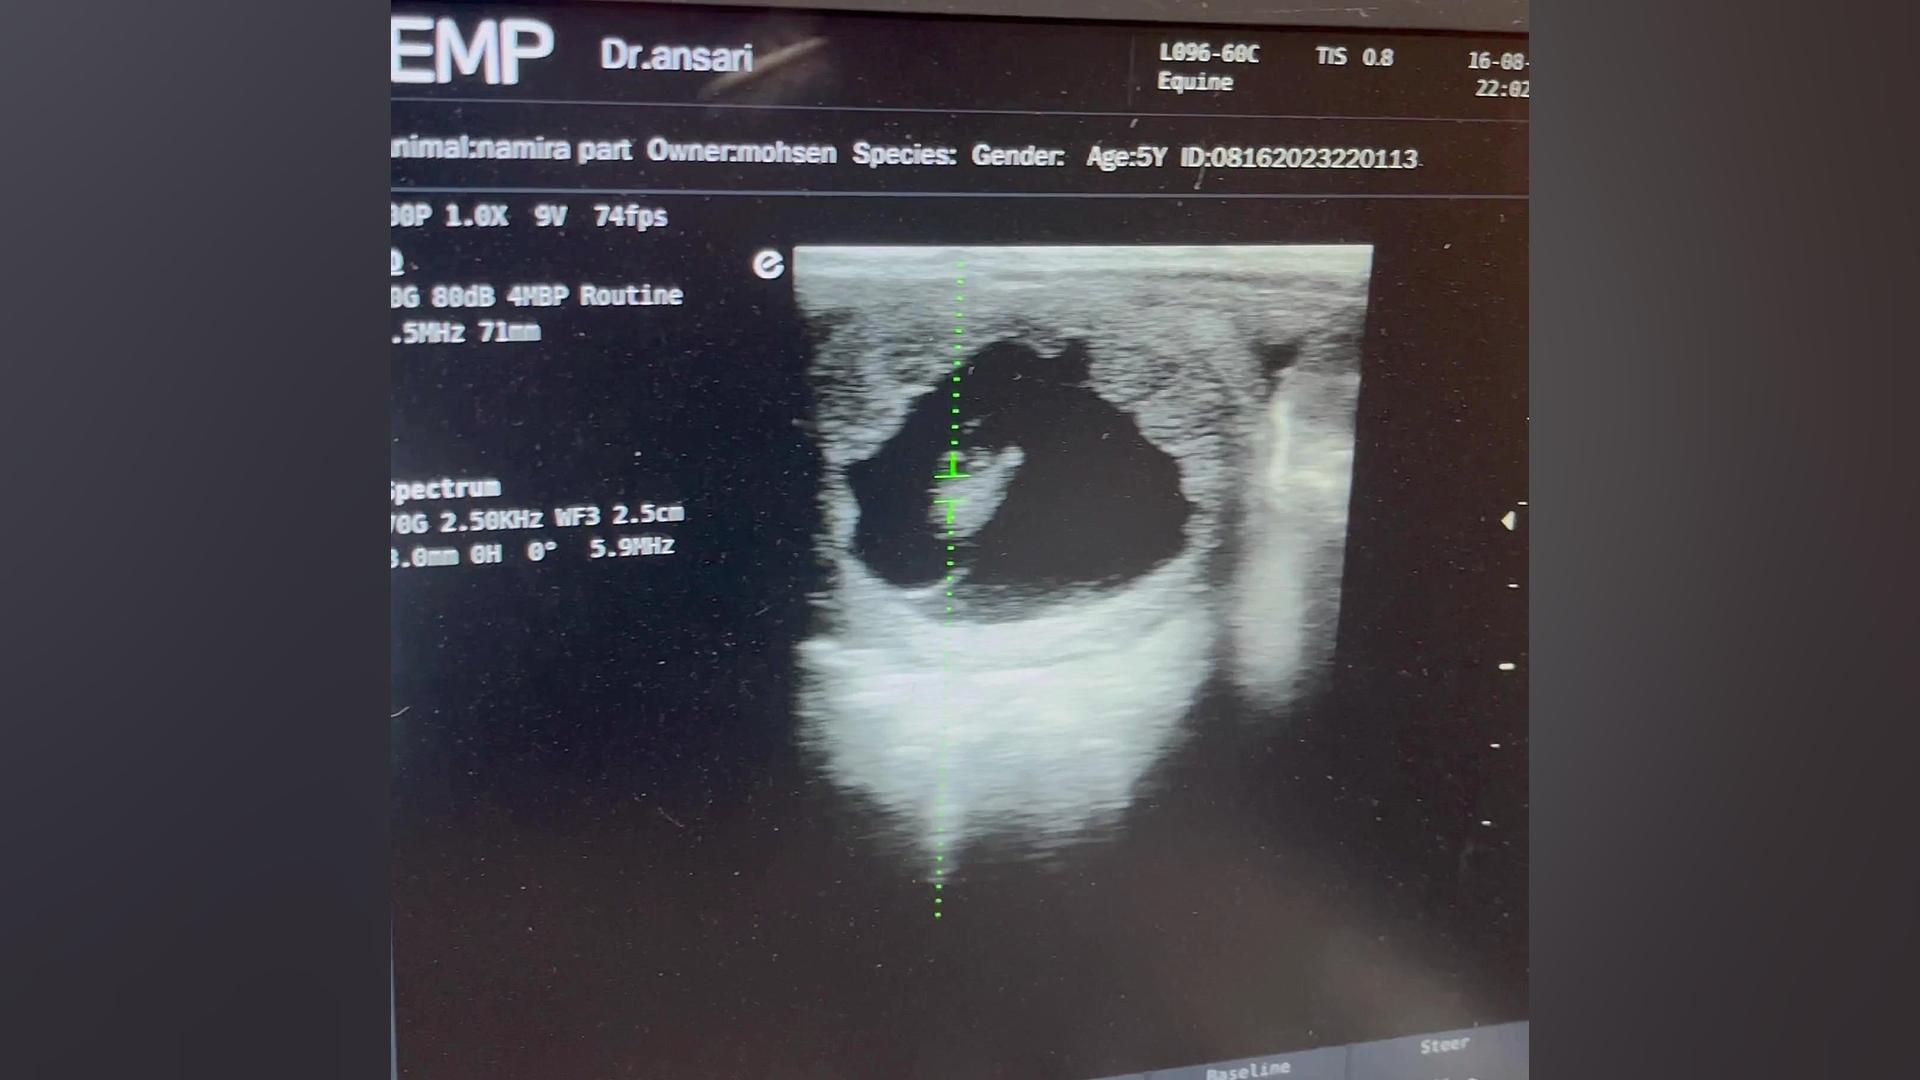

طنین ضربان قلب رویان اسب

2 سال پیش